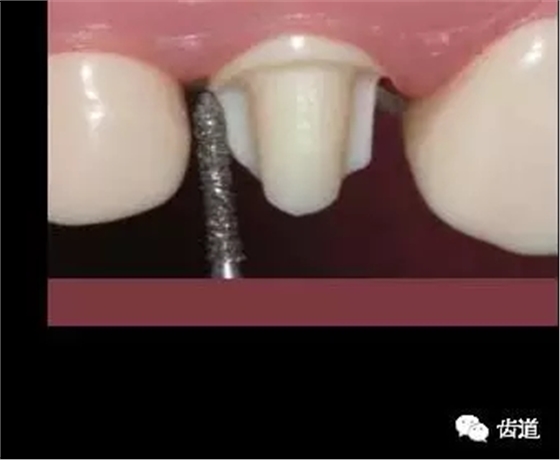

五)就位后調(diào)改順序

1、鄰接(proximal contact): 在人造冠就位的基礎(chǔ)上調(diào)改

3、邊緣適合度(marginal adaptation): 冠邊緣與頸緣間隙<50μm